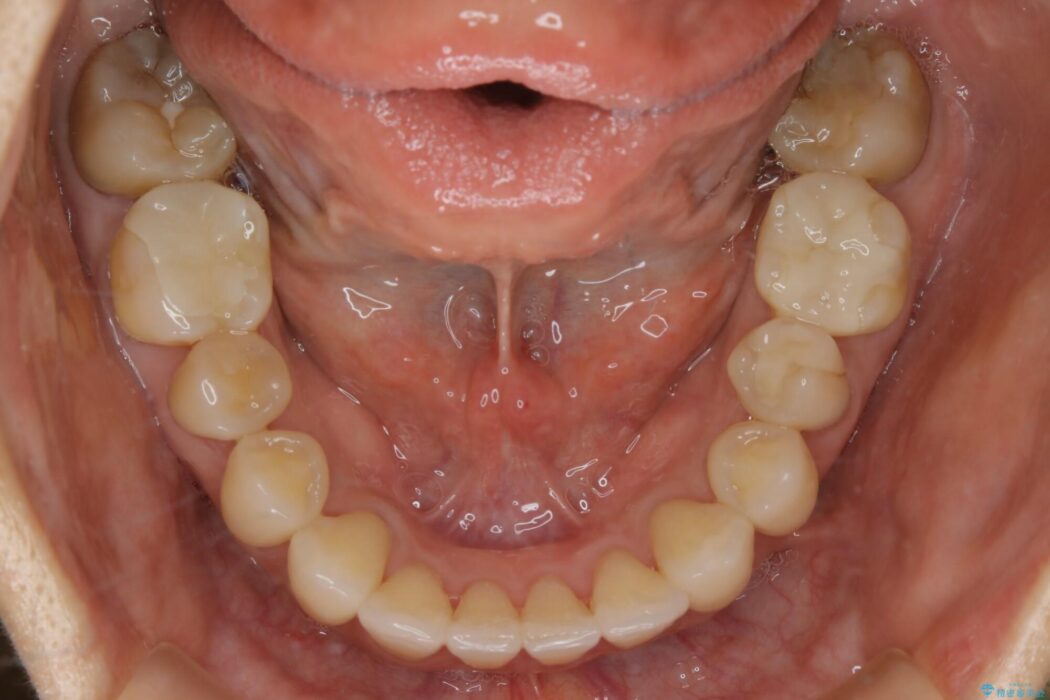

治療後について

気になっていたガタつきも改善され、患者様にはご満足いただけました。